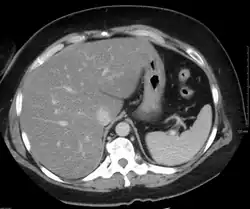

Imaging studies are often obtained during the evaluation process. Ultrasonography reveals a "bright" liver with increased echogenicity. Medical imaging can aid in diagnosis of fatty liver; fatty livers have lower density than spleens on computed tomography (CT), and fat appears bright in T1-weighted magnetic resonance images (MRIs). Magnetic resonance elastography, a variant of magnetic resonance imaging, is investigated as a non-invasive method to diagnose fibrosis progression.[27] Histological diagnosis by liver biopsy is the most accurate measure of fibrosis and liver fat progression as of 2018.[6]